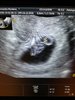

Hey czy mogę dołączyć?? Jestem mamą 5letniej Victorii i 3 letniej Poli po dwóch poronieniach w 2018 roku czekamy na trzeci skarb dokładnie ma przyjść na świat 21.09.2019r ale znając moje szczęście może się przedłużyć :) na ostatnim USG w IP maluszek miał 1,31cm i serduszko biło 164 uderzenia na minutę :) dodaje zdjęcie mojego małego aniołka gdyż pan dr śmiał się że noszę święte dziecko z aureola nad głową :D